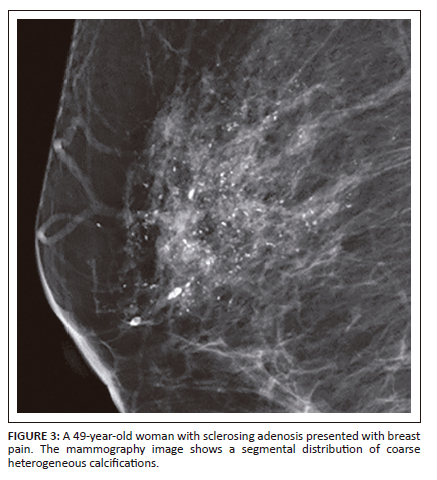

Comparison of the morphology and distribution of suspicious calcifications among DCIS and benign breast disease is demonstrated in Table 2. Fine linear calcifications (Figure 1) were more frequent in DCIS than benign breast disease (6/30 [20%] vs 1/71 [1.4%], respectively). The segmental distribution of calcification (Figure 2 and Figure 3) was more evident in DCIS than benign breast disease (7/31 [23.3%] vs 12/71 [11.9%], respectively), but the regional distribution of calcification (Figure 4) was twice as common in benign breast disease than DCIS (15/71 [21.1%] vs 3/30 [10%]). Amorphous calcifications and grouped distribution were seen in both DCIS and benign breast disease.

In accordance with current knowledge, a segmental or linear distribution of microcalcifications, known as a ductal distribution, is formed within the adjoining terminal ductal lobular units and tends to occur in DCIS.13,14 This study only found a statistically significant correlation with the segmental distribution and DCIS (p = 0.024), as noted in previous studies.11,13,24 However, these studies also demonstrated that a linear distribution had the highest PPV for malignancy. The incongruous result may be explained by the fact that the linear distribution was rarely detected in both groups (2/30 cases in DCIS and 0/71 cases in benign breast disease), resulting in no statistical significance after statistical analysis. Of note, however, the linear distribution was only observed in DCIS calcifications. We found the regional distribution of calcifications more frequently in benign breast disease than in DCIS (p = 0.011). This is related to the fact that these microcalcifications arise in the stromal elements, lobules or glands of the breast and tend to be benign.13,14